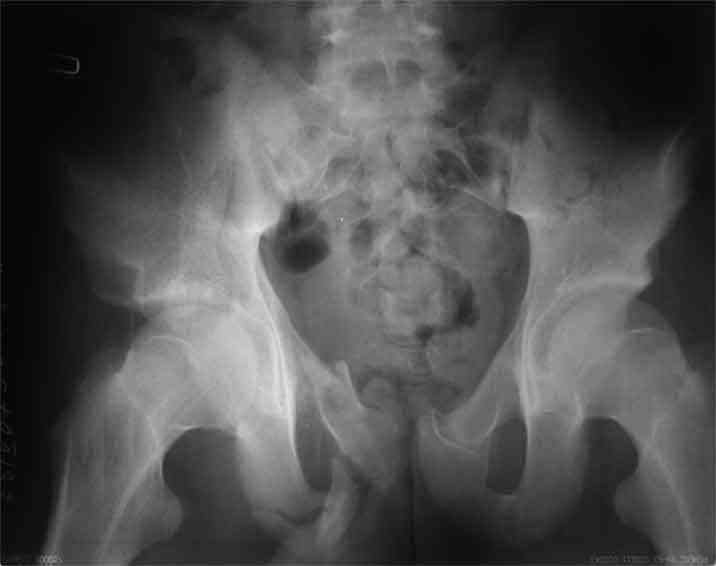

Не смог разглядеть на представленных картинках частичное повреждение левого КП, повреждение Денис1-2 справа? 3Д реконструкции в инлет и боковой проекциях убедительно не демонстрируют типа повреждения задних отделов тазового кольца(справа боковая масса скомпремирована), Наверное, у тебя есть возможность оценить тип перелома крестца по прямой проекции 3Д.

по Pennal et al.- латеральное компрессионное повреждение тип В(ротационно-нестабильное (внутренняя ротация), вертикально стабильное)

по Tile classif. тип В2-1 - частично стабильное повреждение с неполным разрывом задней дуги.

По вертлуге- смог разглядеть только изолированный перелом передней колонны.

В данном случае 3D и корональные срезы КТ менее информативны, чем поперечные. Согласен с левосторенним минимальным повреждением КПС, но не смог уловить перелом крестца.

По представленным материалам, мне кажется, перелом был передней колонны ацетабулум с минимальным вовлечением нагрузочной поверхности сустава, левосторенний повреждение КПС и лонных костей.

Стандартные снимки ацетабулума по Judet и снимки таза (инлет и оутлет) подскажут дальнейшую тактику по нагрузке.